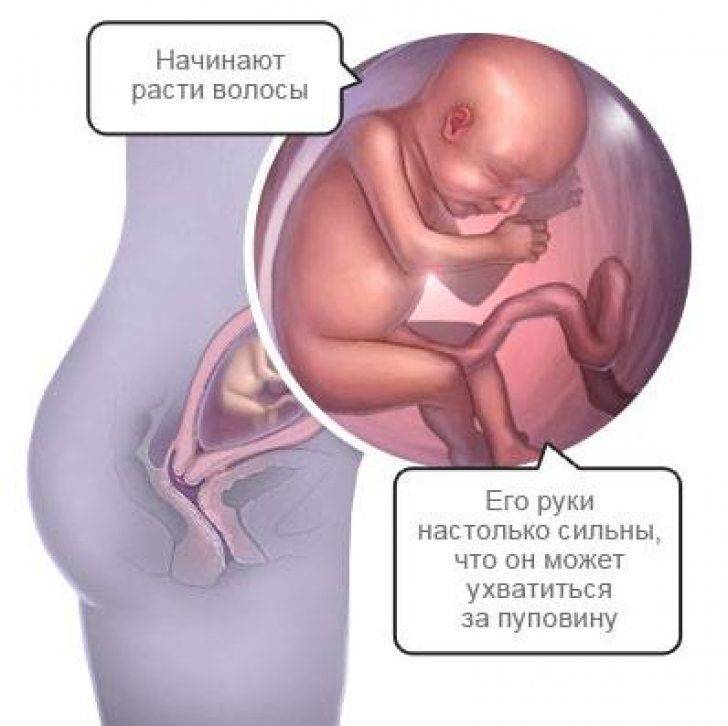

- В этот период волосы малыша отрастают с особой интенсивностью, но их цвет еще не выражен – пока недостаточно меламина вырабатывает его маленькое тельце.

- Быстро развивается головной мозг. Именно в это время малыш начинает изучать себя и то, где он находится с помощью тактильных ощущений. Именно на 22 неделе беременности ребенок пробует шевелить пальчиками, касаться стенок плаценты и себя. Такое исследование ребенком пространства своего обитания будет усиливаться именно на 22 неделе, так что беременная мама будет хорошо ощущать его прикосновения.

- Во время планового УЗИ на 22 неделе беременности на тельце малыша появляются еле заметные волосики, похожие на пух. Они формируют некий вакуум вокруг плода, задерживающий первородную смазку. Кроме этого, смазка защищает ребенка от соприкосновения с водной средой околоплодных вод. Непосредственно перед родами, волосики за ненадобностью исчезают, а предродовая смазка обеспечивает легкий выход малыша из утробы матери.

- Уже на 22 неделе ребенок должен шевелиться, подавая определенные знаки. Теперь уже это непросто проявления рефлекторной физической активности – это осмысленный анализ окружения и обстановки. В это время плод становится очень чувствительным ко всем внешним раздражителям, шуму, музыке разговору, свету и даже свежему воздуху. Теперь он уже непросто переворачивается и изучает окружающую его среду – он выражает свое недовольство или одобрение бурными движениями. Иногда, частое кувыркание младенца в утробе может свидетельствовать о недостатке кислорода, поэтому мамочке нужно трепетно прислушиваться к знакам и вовремя на них реагировать. Но не стоит перебарщивать, воспринимать любое движение ребенка в качестве недовольства или желания. Во время сна, а это большая часть времени, малыш не активен. Зато утром и вечером может разводить бурную деятельность. Проблема в том, что биологические часики плода не всегда совпадают с фактическими утренними и вечерними часами. Это для мамы не всегда комфортно. Слишком спокойное поведение ребенка тоже должно немного настораживать, а в отсутствие малейших движений более двух суток – нужно обязательно показаться врачу.

Малыш старается изучить окружающую его среду. Поэтому с каждым днем его движения в матке становятся все более разнообразными. На этой неделе он ежедневно совершает около двухсот движений. Но мамочка замечает только самые сильные.

Интенсивность его движений зависит от того, в какой обстановке находится мама. Слишком яркий свет и шум заставляют его чаще двигаться. Помимо этого немаленькую роль играет эмоциональное состояние мамы.

Иногда беременные замечают небольшие ритмичные постукивания. Это — результат икания малыша.